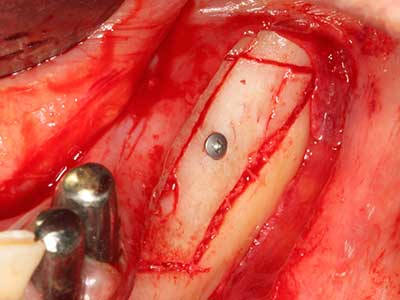

Sollen chirurgische Eingriffe mit unmittelbarer Knochenbeziehung an empfindlichen Strukturen wie Blutgefäßen oder Nerven erfolgen, so bergen rotierende Instrumente ein erhebliches Potential an iatrogener Schädigung. Gerade bei Nervdarstellungen nach iatrogener Schädigung, oder aber im Zuge einer Nervlateralisation für resektive und rekonstruktive Eingriffe oder Implantatinsertionen können piezoelektronische Geräte hilfreich sein Knochendeckel zu präparieren und nervnahe Hartgewebsanteile zu entfernen (Abb. 17-20). Ein leichter Kontakt des Nervstrangs zur Piezospitze bleibt dabei in der Regel folgenlos – allerdings kann eine unvorsichtige Vorgehensweise mit sägeartigen Bewegungen bzw. Ansätzen bei noch vorhandener knöcherner Unterlage durchaus temporäre oder aber auch permanente Nervschädigungen verursachen. Das Risiko einer solchen Schädigung wird jedoch als wesentliche geringer eingeschätzt als unter Anwendung von Säge- oder Fräsinstrumenten (Pereira, Gealh et al. 2014).